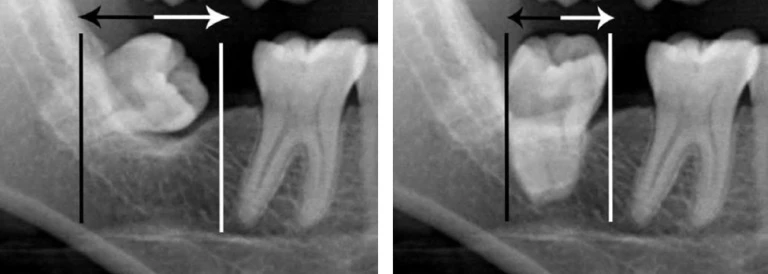

Tạo khoảng trong chỉnh nha, các răng sau bị nghiêng luôn chiếm nhiều khoảng trống hơn. Các răng cối lớn có khuynh hướng nghiêng gần khi răng cối sữa thứ hai bị mất sớm hoặc bị sâu răng ở mặt xa không được phục hồi vào thời điểm thích hợp hoặc có bờ viền miếng trám chưa tốt. Mọc chậm răng cối nhỏ thứ nhất hoặc thứ hai cũng khiến cho răng sau nghiêng gần.

Dựng trục răng cối lớn có thể tăng độ dài cung răng từ 1-1.5mm. Các khí cụ cố định lý tưởng được dùng cho mục đích này. Các khí cụ hoặc vít tạo khoảng khác nhau cũng được dùng thường xuyên. Lip bumper và biến thể của nó cũng có thể mang lại kết quả tốt.

Hình 5. Răng cối lớn nghiêng gần chiếm nhiều khoảng trống hơn, dựng trục răng cối phía sau giúp tạo lại khoảng